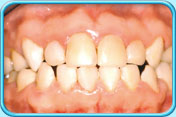

有橙色漬的牙齒牙齒沒給清潔乾淨,積聚在表面的牙菌膜含有一些能發出顏色的細菌或真菌,形成綠色或橙色的漬。

牙科醫生會藉洗牙以清除積聚的牙菌膜及色素。

清除橙色漬後的牙齒每天早晚刷牙和使用牙線徹底清除牙菌膜,以保持牙齒潔白。